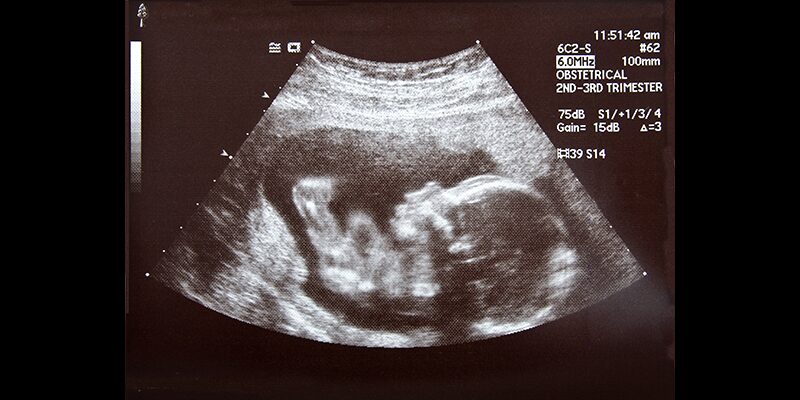

Unfortunately, even with Derbyshire’s admission that science is on the side of Life, he has refused to reevaluate his anti-Life position. According to Derbyshire, lackey of the abortion industry worldwide, the appropriate response to the clear and compelling evidence that preborn babies feel pain long before the legal limit for elective abortion in much of the world is to tell mothers undergoing elective abortion about the possibility of fetal pain and ask if they would like to administer medication to make the fatal procedure less painful for their child. This is unlikely to gain traction in the abortion industry, which has ignored advances in sonogram technology and continues to claim that babies in the womb are “clumps of cells.” Telling mothers how advanced and highly developed the child is they are considering aborting would certainly be bad for business.